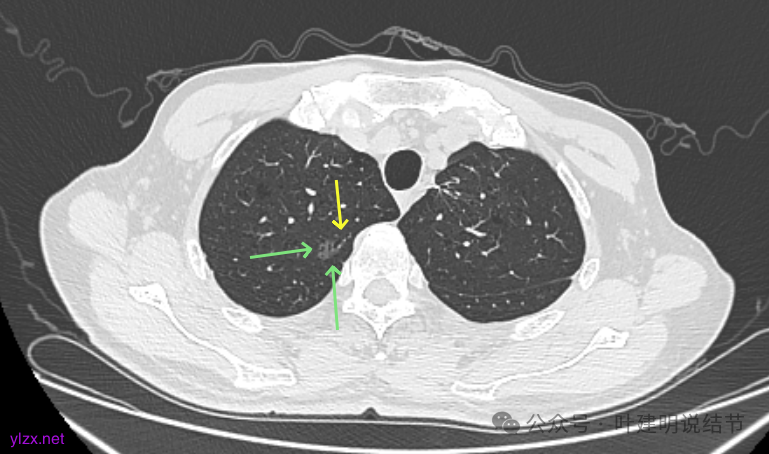

再看2024年9月复查的:

右上的仍小而淡,轮廓仍是清楚的。

左上的病灶略显模糊,密度不太纯,较前相仿。

再看2024年9月的:

右上的较前略增大,且有空泡征较豙明显些,肿瘤的成分仍是纯磨密度。

左上病灶也是较为纯的,边缘不光滑,大小似乎略大一点点,不太显著。